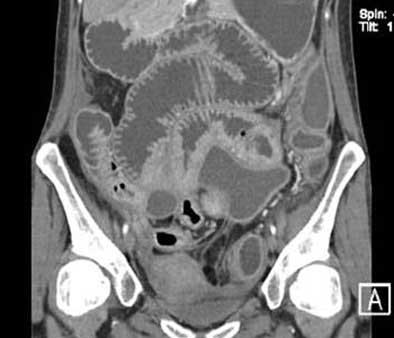

| All images are of a 21-year-old woman who presented with symptoms typical of Crohn's disease: recurrent episodes of hemorrhagic diarrhea, abdominal pain, weight loss, and fever. Endoscopy showed segmental changes in the colon and the terminal ileum; histopathology showed granulomatous mucosal inflammation. In image above, normal enteroclysma CT, coronary reconstruction, shows optimal distension of small-bowel loops. All images courtesy of Dr. Johannes Sailer and Dr. Philipp Peloschek, Department of Radiology, Medical University of Vienna. The group will present its CT enteroclysis results later this month at RSNA scientific presentation presentation No. SSQ06-06). |